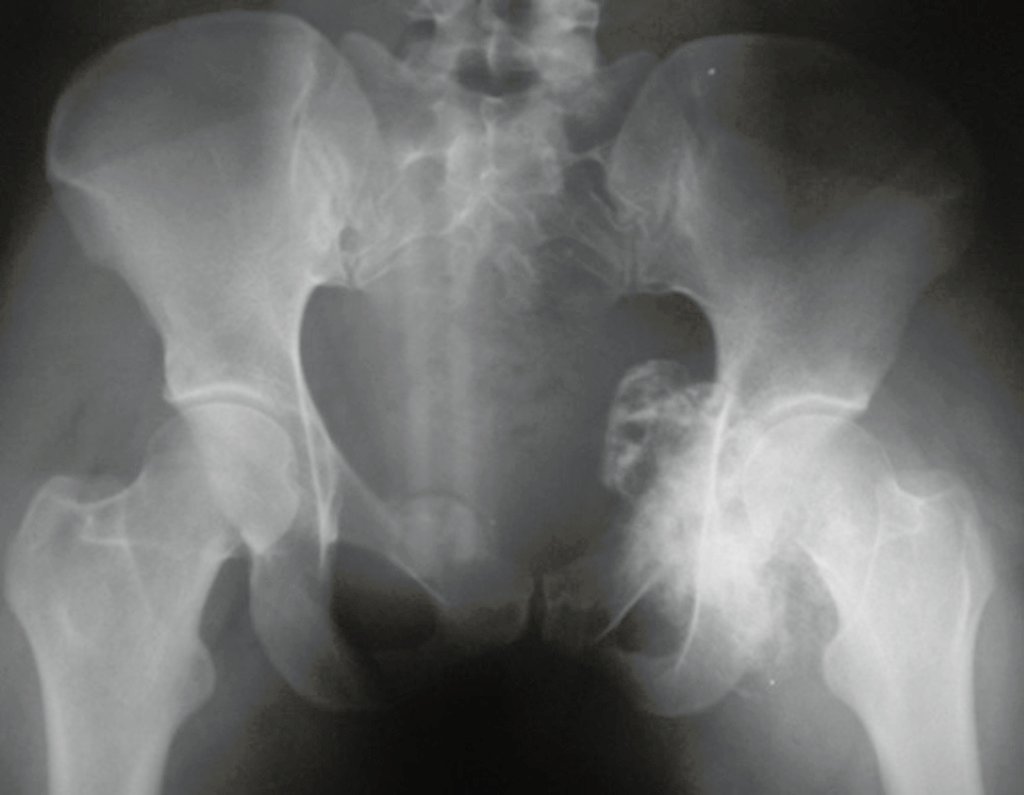

Chondrosarcoma occurs in bones of endochondral origin, mainly in the roots of the limbs: shoulder (Figures 1 to 3), pelvis (Figures 4 to 10), ribs and axial skeleton 1 , being rare in bones of membranous origin 11,14,15 ,24.

Figures 1 to 10 illustrate large chondrosarcomas of the shoulder girdle and pelvic girdle, which evolved slowly.